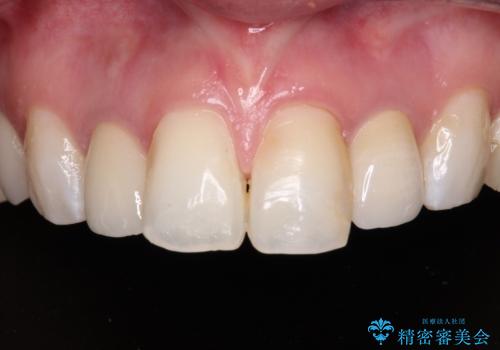

金属の見えてしまったクラウン セラミッククラウンで自然に